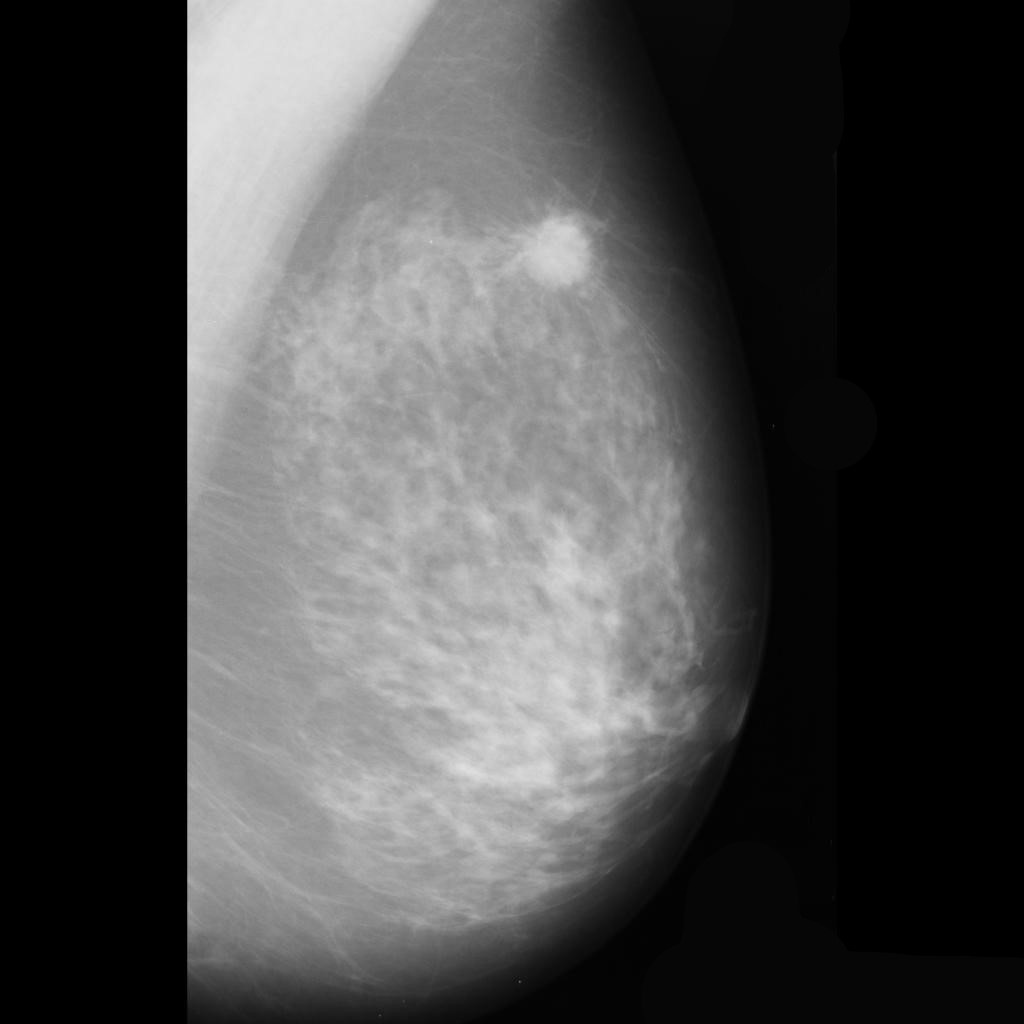

malignant